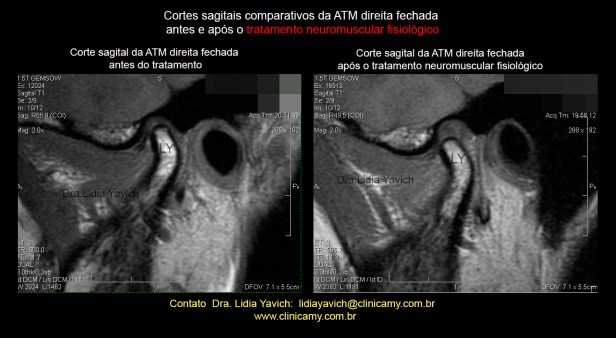

RNM: cortes sagitais comparativos da ATM direita, boca fechada, antes e após o tratamento Neuromuscular Fisiológico. Neste corte se aprecia a melhora na relação côndilo discal obtida.

RNM: cortes sagitais comparativos da ATM direita, boca fechada, antes e após o tratamento Neuromuscular Fisiológico. Neste corte se aprecia a melhora na relação côndilo discal obtida.

Nota-se a descompressão tridimensional da articulação. Objetivo primordial neste caso específico.

RNM: cortes sagitais comparativos da ATM direita, boca fechada, antes e após o tratamento Neuromuscular Fisiológico. Neste corte se aprecia a melhora na relação côndilo discal obtida.

RNM: cortes sagitais comparativos da ATM direita, boca fechada, antes e após o tratamento Neuromuscular Fisiológico. Neste corte se aprecia a melhora na relação côndilo discal obtida.

Nota-se a descompressão tridimensional da articulação. Objetivo primordial neste caso específico.

RNM: cortes sagitais comparativos da ATM direita, boca fechada, antes e após o tratamento Neuromuscular Fisiológico.Neste corte se aprecia a melhora na relação côndilo discal obtida.

RNM: cortes sagitais comparativos da ATM direita, boca fechada, antes e após o tratamento Neuromuscular Fisiológico.Neste corte se aprecia a melhora na relação côndilo discal obtida.

Nota-se a descompressão tridimensional da articulação. Objetivo primordial neste caso específico.